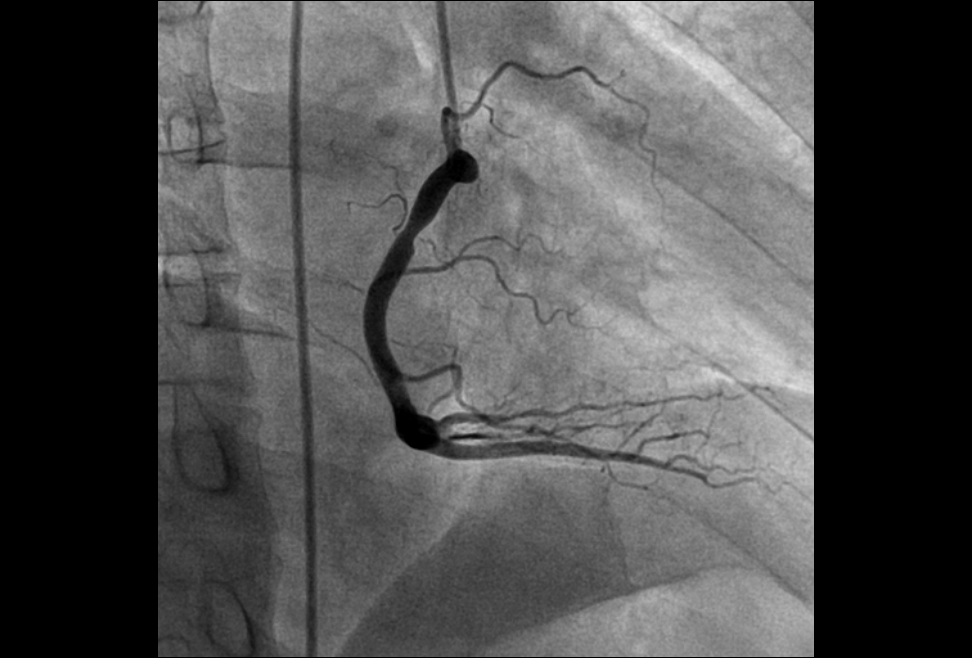

1.心血管介入手术治疗:可以完成冠状动脉造影术,PTCA支架术,二尖瓣球囊扩张术,射频消融术,起搏器植入术,先天性心脏病介入治疗,冠状动脉腔内溶栓术等微创介入手术。

病患的右冠狭窄 通过DSA支架植入 有冠状动脉恢复正常供血,病人病情缓解